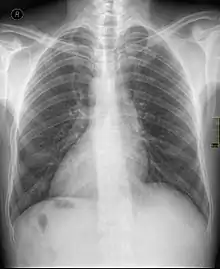

Chest X ray of a person with dextrocardia situs inversus showing the cardiac apex pointing towards right

Dextrocardia (from Latin dextro, meaning "right hand side," and Greek kardia, meaning "heart") is a rare congenital condition in which the apex of the heart is located on the right side of the body, rather than the more typical placement towards the left.[1] There are two main types of dextrocardia: dextrocardia of embryonic arrest (also known as isolated dextrocardia) and dextrocardia situs inversus. Dextrocardia situs inversus is further divided.